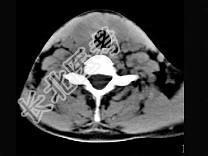

- 单项选择题40岁,女性患者, 双侧甲状腺肿大,CT扫描如图所示, 请选择最佳答案 ( )

A、弥漫性甲状腺肿

B、甲状腺癌

C、甲状腺炎(桥本)

D、亚急性甲状腺炎

E、甲状腺瘤